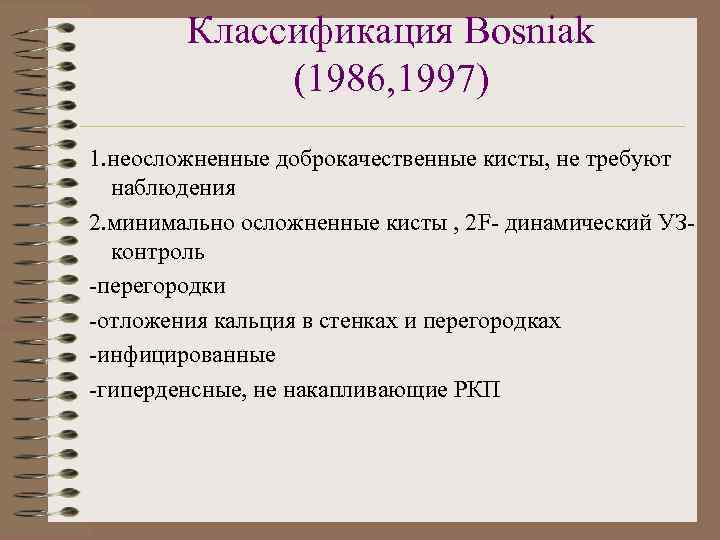

Классификация Bosniak (1986, 1997) 1. неосложненные доброкачественные кисты, не требуют наблюдения 2. минимально осложненные кисты , 2 F- динамический УЗконтроль -перегородки -отложения кальция в стенках и перегородках -инфицированные -гиперденсные, не накапливающие РКП